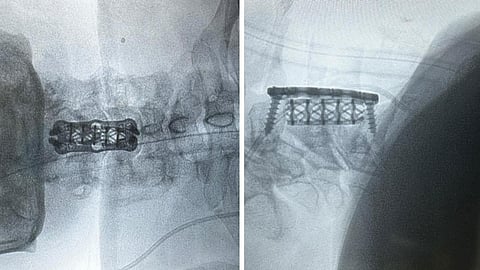

وبعد إجراء الفحوصات الطبية اللازمة تبيّن وجود ضغط على الحبل الشوكي بسبب الغضاريف بين الفقرات الثالثة والرابعة العنقية، ونتوءات عظمية خلف الفقرة العنقية الرابعة، حيث قام الفريق الطبي بقيادة استشاري جراحة العظام وجراحة العمود الفقري الدكتور متعب أبو راس بإزالة الغضروف مع استئصال جزئي للفقرة الرابعة؛ لتحرير الحبل الشوكي، ليتم بعدها تثبيت الفقرات بنجاح، وتحسنت حالة المريض تماماً بعد العملية الجراحية ولله الحمد.